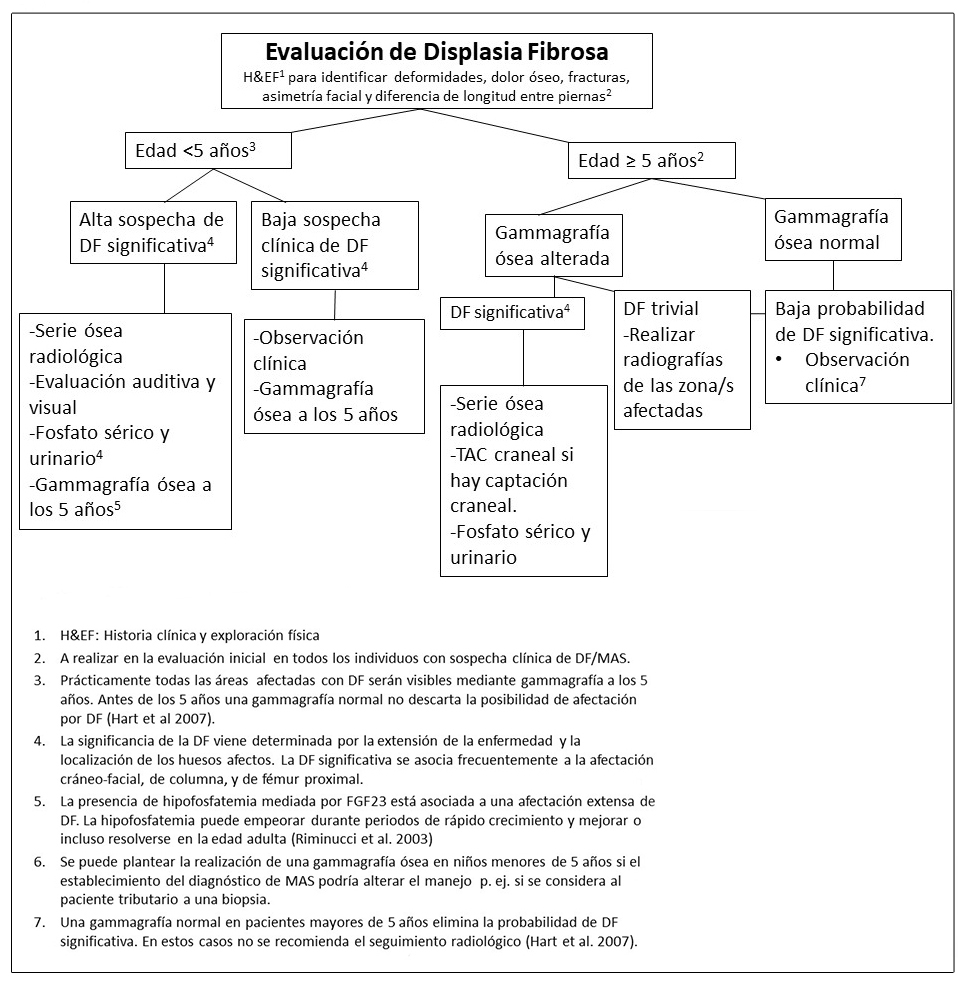

En la Figura 3 se exponen las pruebas de evaluación recomendadas para el diagnóstico de DF.

Figura 3. Pruebas y seguimiento recomendado tras el diagnóstico inicial en individuos con Displasia Fibrosa / Síndrome de McCune-Albright

(1) Ver Figura 3 en la que se exponen los estudios recomendados para evaluar el esqueleto tras el diagnóstico. ORL: sistema otorrinolaringológico; RGE: reflujo gastro-esofágico.